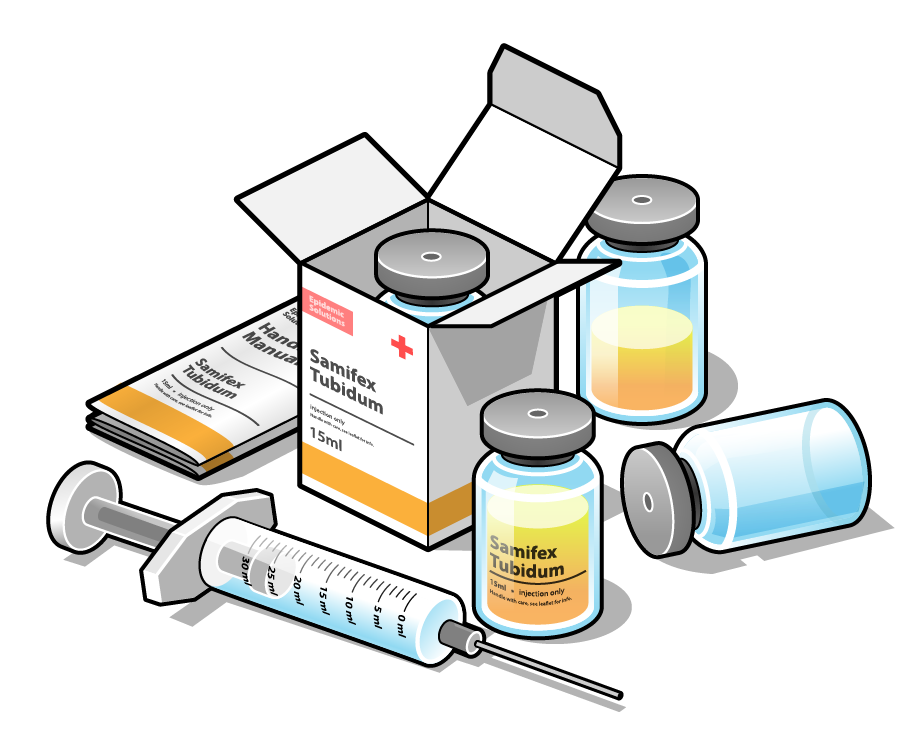

2000x1514 Placebo Induced Somatic Sensations A Multi Modal Study Of Three

585x1020 Free Body Diagram Templates Sample, Example, Format Download